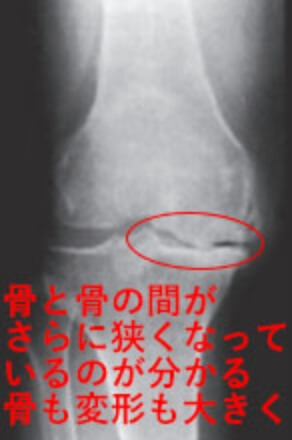

3 変形性膝関節症の進行期。

膝関節の隙間がさらに狭く(50~75%)なったり、はっきり確認できる程の骨棘や骨硬化が生じたりする。

K-L分類Grade3のX線画像